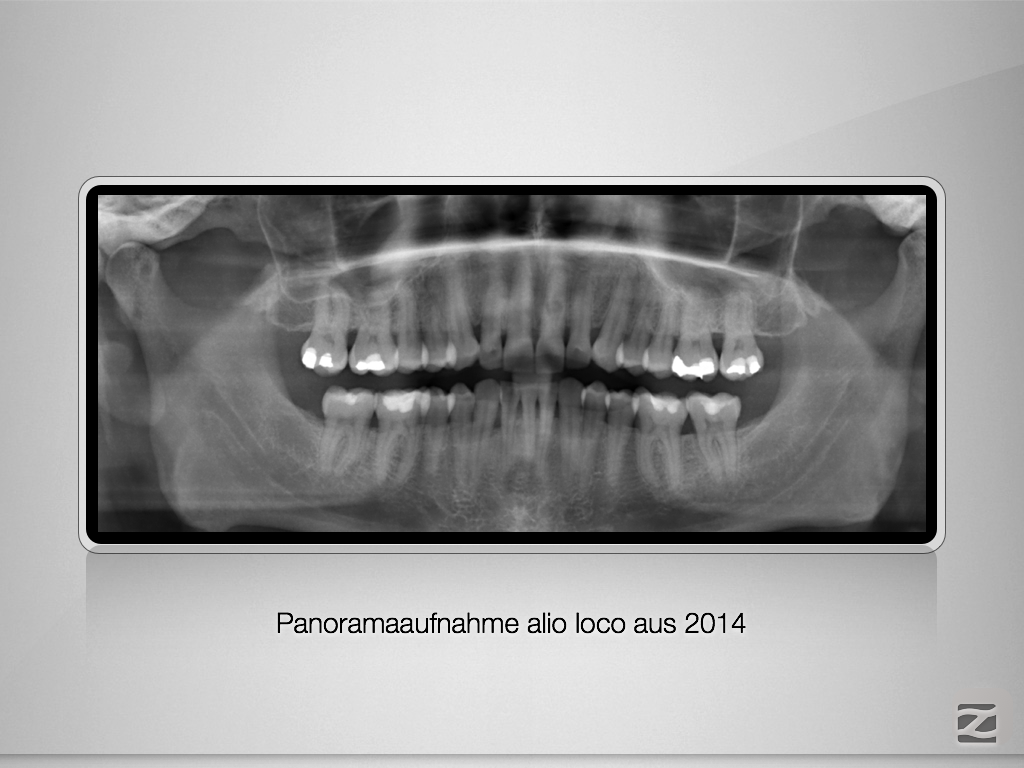

Wie eine Pulpanekrose einen Zahn retten kann.